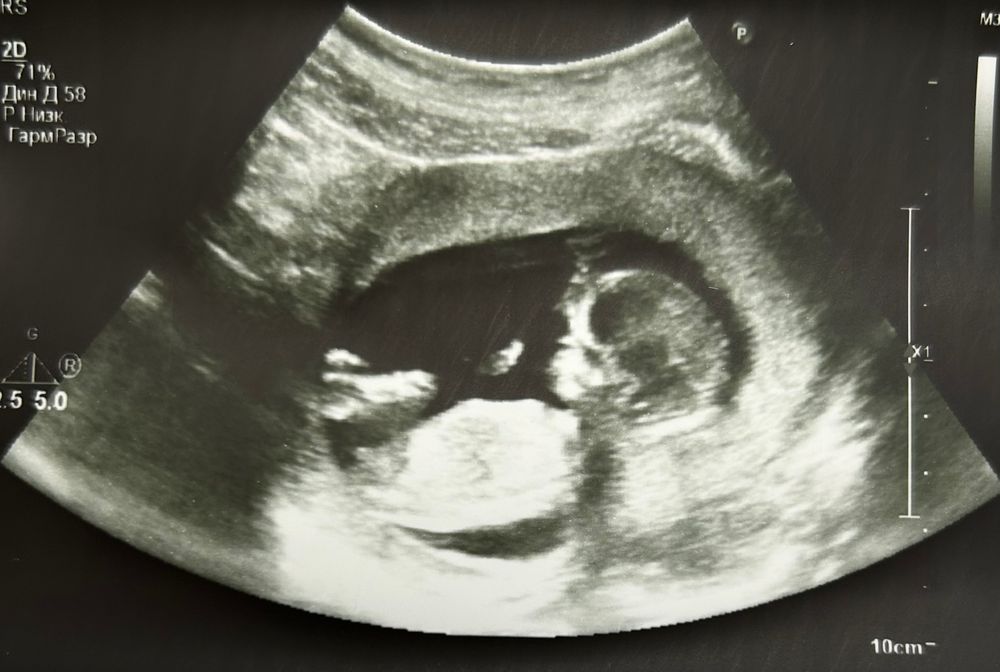

УЗИ на 13 неделе

На девочку похоже.У меня на первом скрининге то бугорок в верх торчал ,а у вас прямо.

Как будто больше на девочку смахивает бугорок)) но кто знает;) у меня у мальчишек помню выше торчал

бугорок вижу, но не уверена 100% но я бы подумала что мальчик)

Мальчишка

Мне кажется мальчик 🩵

Мальчика вижу )

В итоге - девочка!)